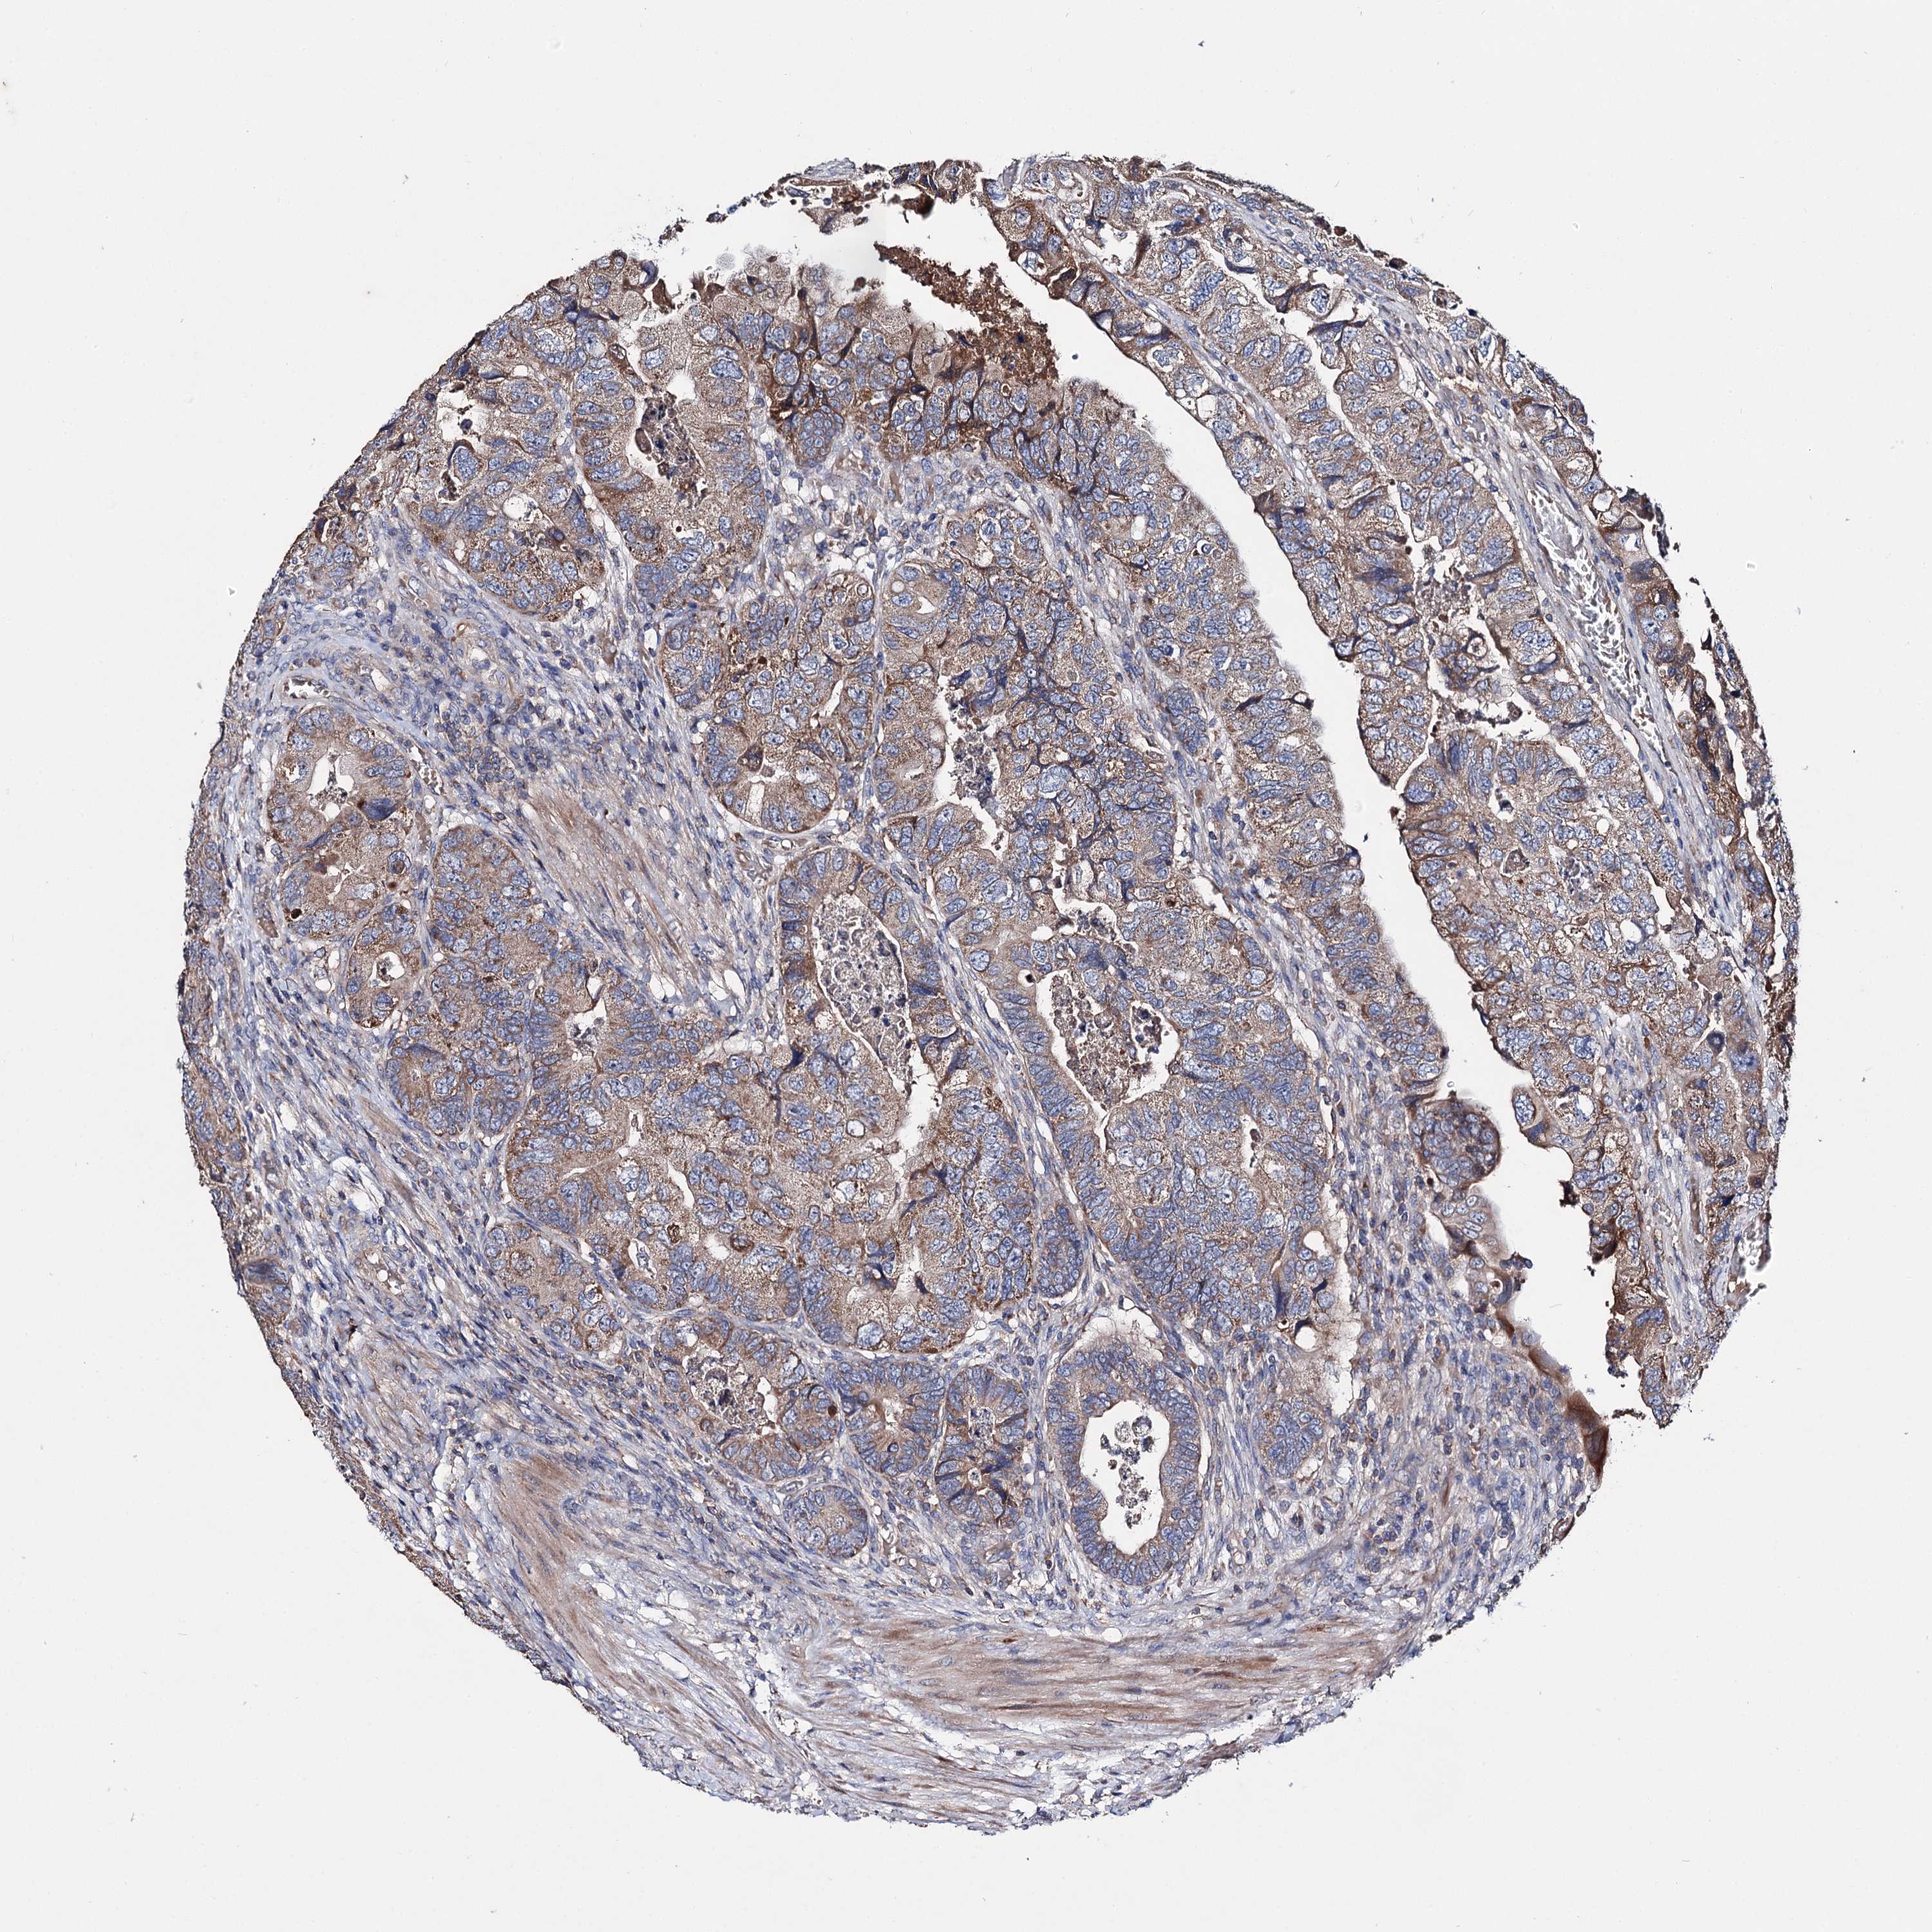

CANCER COLORECTAL CANCER Show tissue menu

Colorectal cancer

Human cancer

Colon adenocarcinoma

Rectum adenocarcinoma